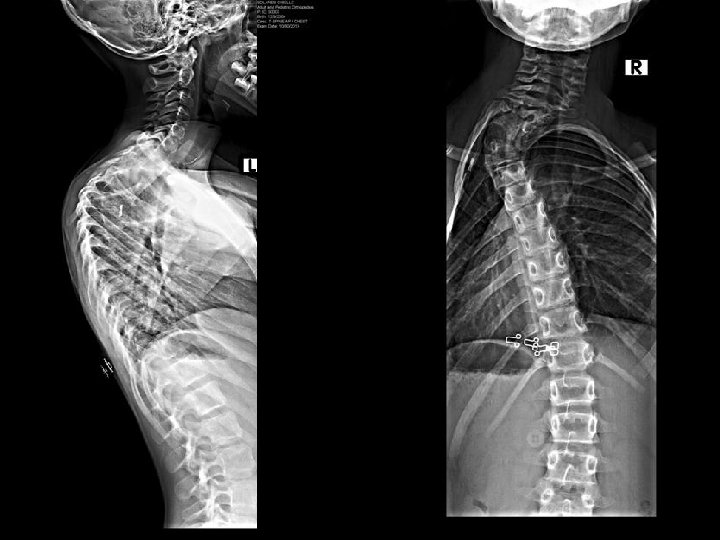

Case # 2 G. S. is a 8 year 10 month old female with a history of neuroblastoma left side of chest diagnosed in 2007. She completed chemotherapy followed by resection of the tumor in 2007. She developed progressive cervicothoracic kyphotic deformity. She was complaining of esophageal pressure with nausea. She had no neurological abnormalities, except for dysesthesias left axilla and left thorax. X rays, MRI, and computed tomography follow:

• The surgical procedure consisted of vertebral column resection with kyphectomy at T 4, posterior spinal arthrodesis from T 1 to T 6, and segmental spinal instrumentation from C 5 to T 10 in a guided growth construct. • One year post-op the growth from T 1 to T 12 was 0. 9 cm. , and the growth from T 1 to S 1 was 2. 6 cm. based on Surgimap spine software (Nemeric, Inc. ).

Post-op

One year post-op